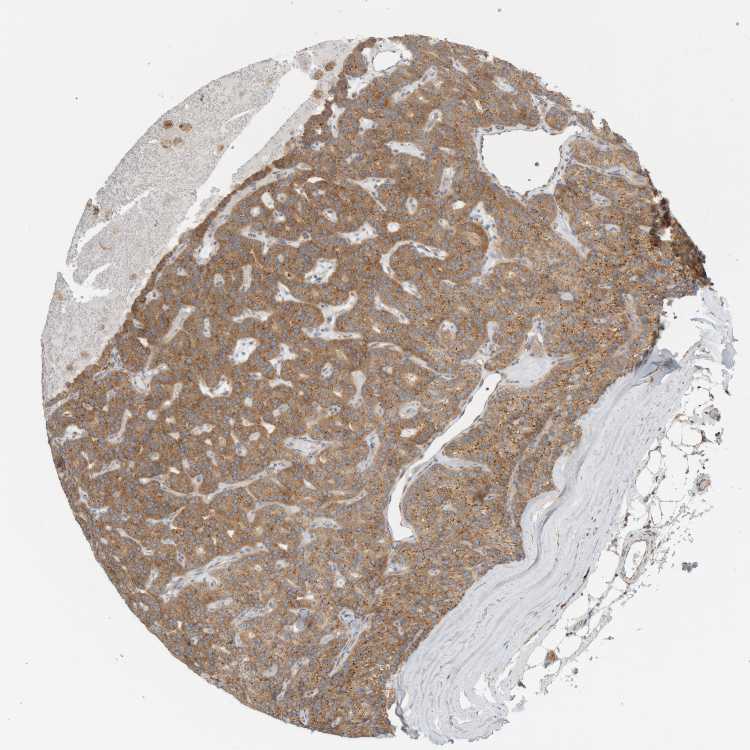

PARATHYROID GLAND - Antibody stainingi

Antibody staining in the annotated cell types in the current human tissue is reported as not detected, low, medium, or high, based on conventional immunohistochemistry profiling in selected tissues. This score is based on the combination of the staining intensity and fraction of stained cells.

Each image is clickable and will lead to virtual microscopy that enables deeper exploration of all samples and also displays staining intensity scores, fraction scores and subcellular localization as well as patient and tissue information for each sample.

Antibody HPA008297Antibody HPA025922Antibody CAB019277

Glandular cells MediumMediumHigh